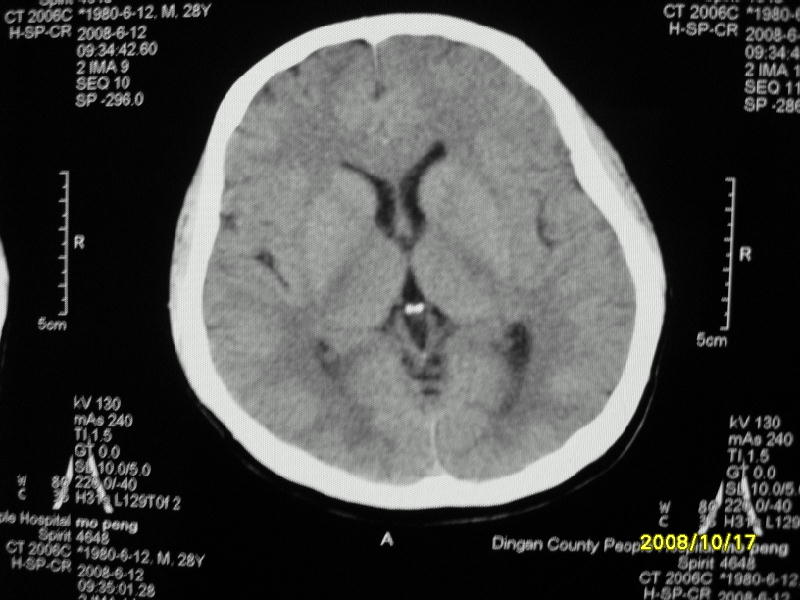

检查名称:     ct颅脑平扫           男     28岁

表现:左顶叶见斑点状致密影。边缘清,大小约0。3*1。0cm,余脑实质密度及灰白质结构示见异常。脑室系统大小,形态,密度未见异常。脑沟。脑裂。脑池未见异常密度影。中线结构无移位。

印象:左顶叶少许钙化灶